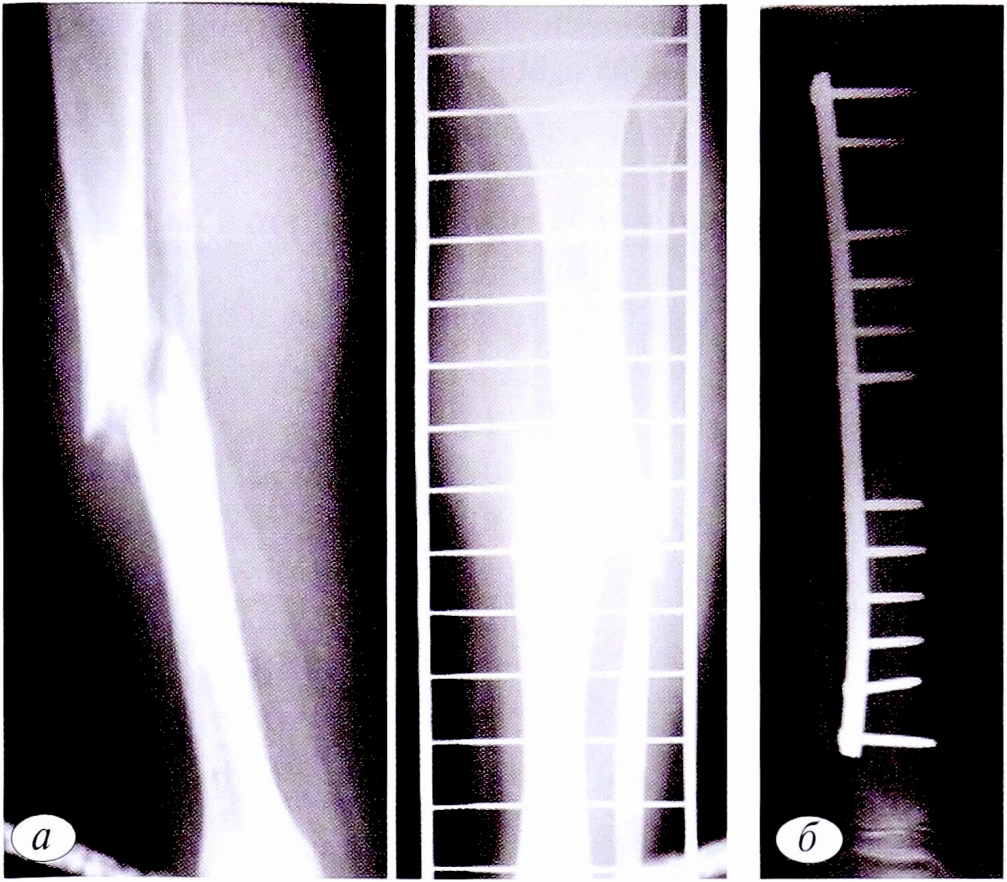

Патологические переломы при неостеогенных фибромах происходили в 7 случаях, в том числе 4 со смещением,3 без смещения. Они были связаны как с бессимптомным течением самого заболевания, так и с недооценкой угрозы возникновения патологического перелома при ранее выявленном патологическом очаге. В случаях, когда течение заболевания было осложнено патологическим переломом, тактика лечения зависела от наличия смещения костных отломков. При его отсутствии допускалось консервативное лечение гипсовыми повязками. Поскольку сроки сращения патологических переломов при неостеогенных фибромах аналогичны установленным срокам при высокоэнергетических травматических переломах, а патологический очаг оставался в неизмененном виде, то после консолидации перелома выполняли костно-пластическую операцию. При наличии смешения костных отломков применяли открытую репозицию, краевую резекцию, аллопластику и фиксацию перелома пластиной или аппаратом внешней фиксации (рис. 4).

Рис. 4. Пациентка С.,16 лет. Диагноз: патологический перелом нижней трети левой большеберцовой кости на фоне неостеогенной фибромы. а — рентгенограммы костей левой голени в 2 проекциях до операции; б — после операции: открытая репозиция, краевая резекция нижней трети левой большеберцовой кости, аллопластика, металлоостеосинтез.

Fig. 4. Patient S.,16 years old. Diagnosis: pathological fracture of the lower third of the left tibia due to non-osteogenic fibroma. a — radiographs of the bones of the left tibia in 2 projections before surgery; б — radiographs of the bones of the left lower leg after surgery: open reduction, marginal resection of the lower third of the left tibia, alloplasty, metallosteosynthesis.